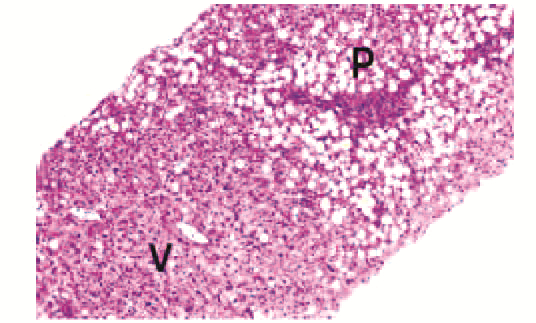

非酒精性脂肪性肝病儿童肝组织病理特征分析

刘敏, 陈卫坚, 周峥珍, 覃小梅, 文容, 姜楠, 匡林芝, 郑台青, 张丽琼, 李双杰

2023, 39(5): 1144-1149. DOI: 10.3969/j.issn.1001-5256.2023.05.021

摘要(861) HTML (394) PDF (3065KB)(80)

摘要: